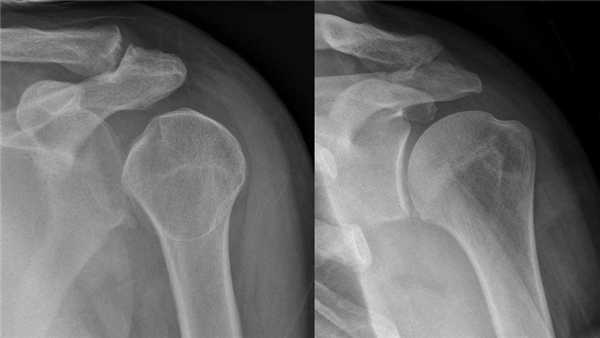

Признаки нижнего вывиха плеча (luxatio erecta)

Вывих плеча может сочетаться с переломом головки, анатомической или хирургической шейки плеча, отрывом малого или большого бугорка плечевой кости, переломом суставной впадины, акромиального или клювовидного отростков лопатки, повреждением расположенных рядом сухожилий, сосудов и нервов. При сочетании вывиха с другой травмой говорят об осложненном вывихе плеча. В зависимости от направления смещения головки плечевой кости выделяют передние, задние и нижние вывихи плеча. Чаще всего (3/4 случаев) встречается передний вывих плеча. Второе место по частоте занимает нижний вывих плеча (около 20%).

При переднем вывихе плеча головка смещается вперед и вниз. Рука находится в вынужденном положении (отведена в сторону или согнута, отведена и развернута кнаружи). При пальпации головка плечевой кости не обнаруживается на обычном месте, может прощупываться в передних отделах подмышечной впадины (при передненижних вывихах) или ниже клювовидного отростка лопатки. Передние и передненижние вывихи плеча иногда сопровождаются отрывом большого бугорка плечевой кости, переломом клювовидного или акромиального отростков лопатки.

При нижнем вывихе плеча головка смещается в подмышечную впадину. В подмышечной впадине проходят сосуды и нервы. Если головка сдавливает сосудисто-нервный пучок, возникает онемение кожи и паралич мышц в области, которую иннервирует сдавленный нерв. Для заднего вывиха плеча характерно смещение головки в сторону лопатки.